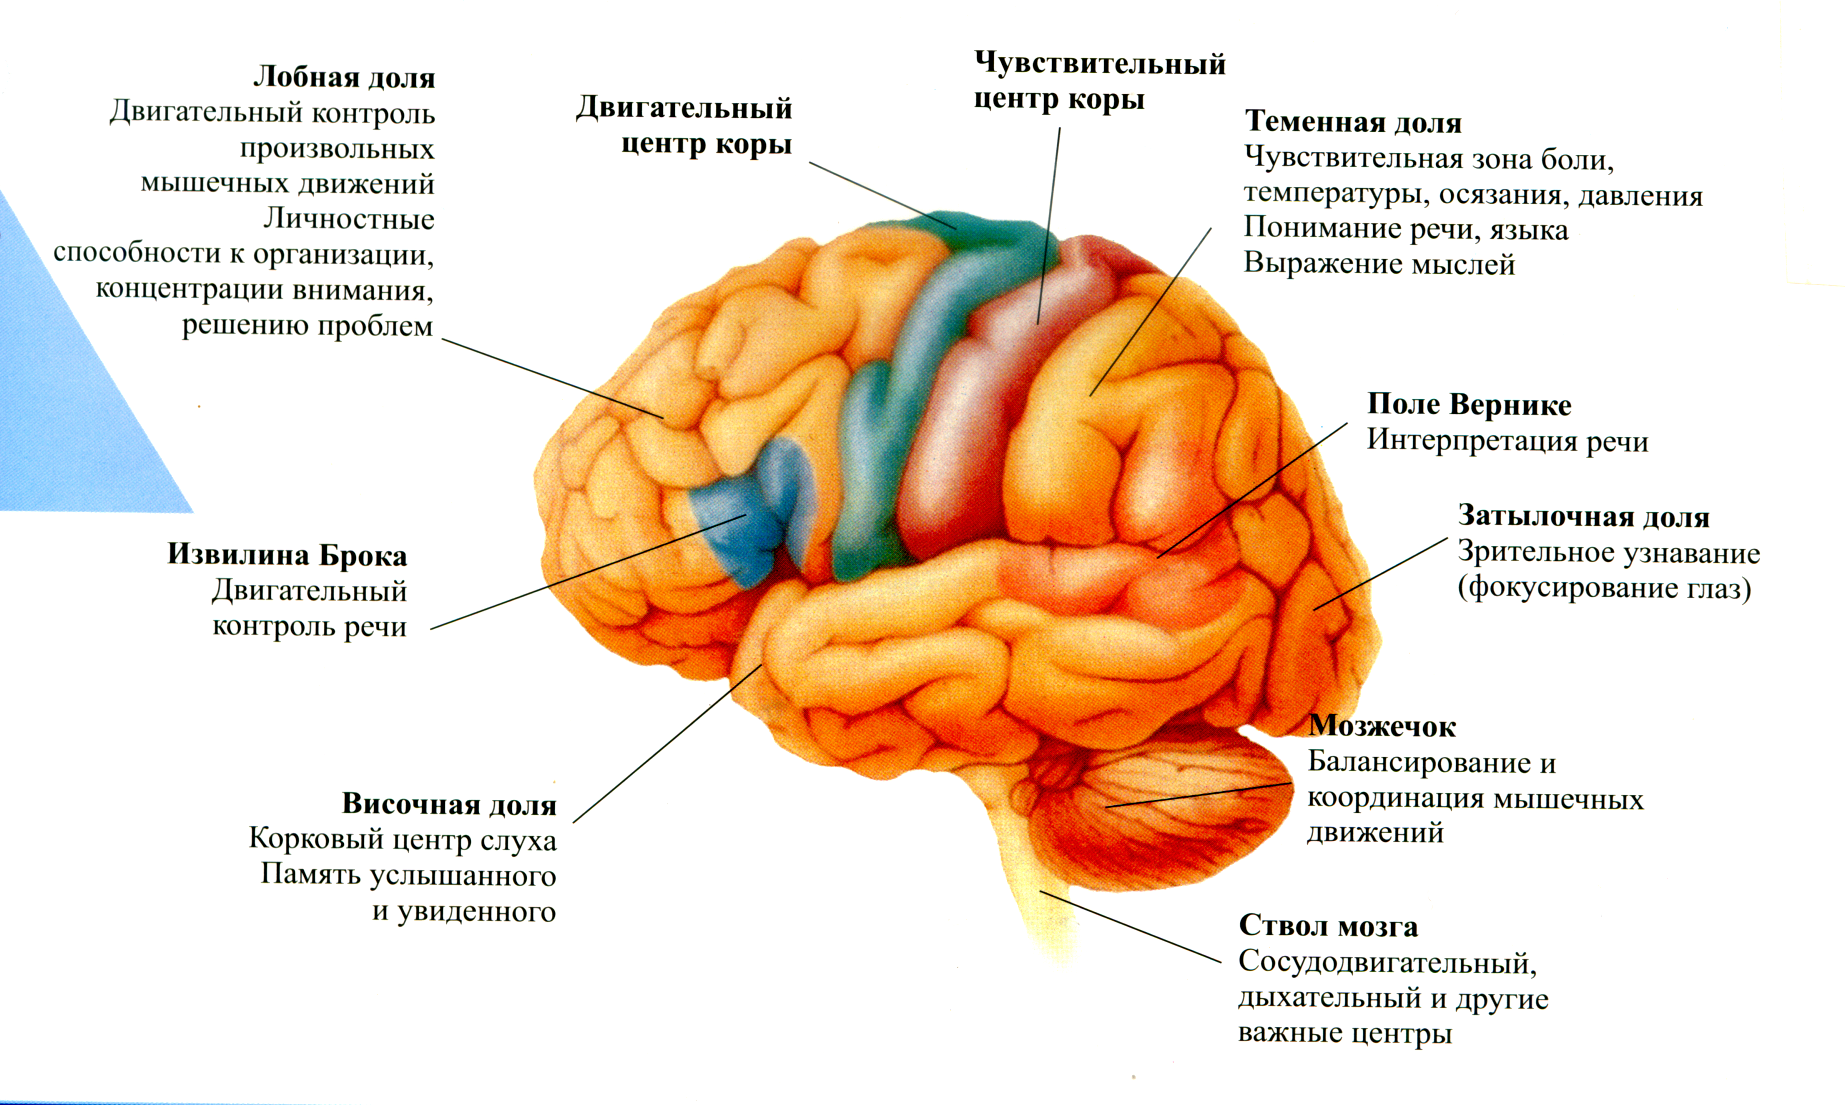

Схема чувствительных зон новой коры мозга